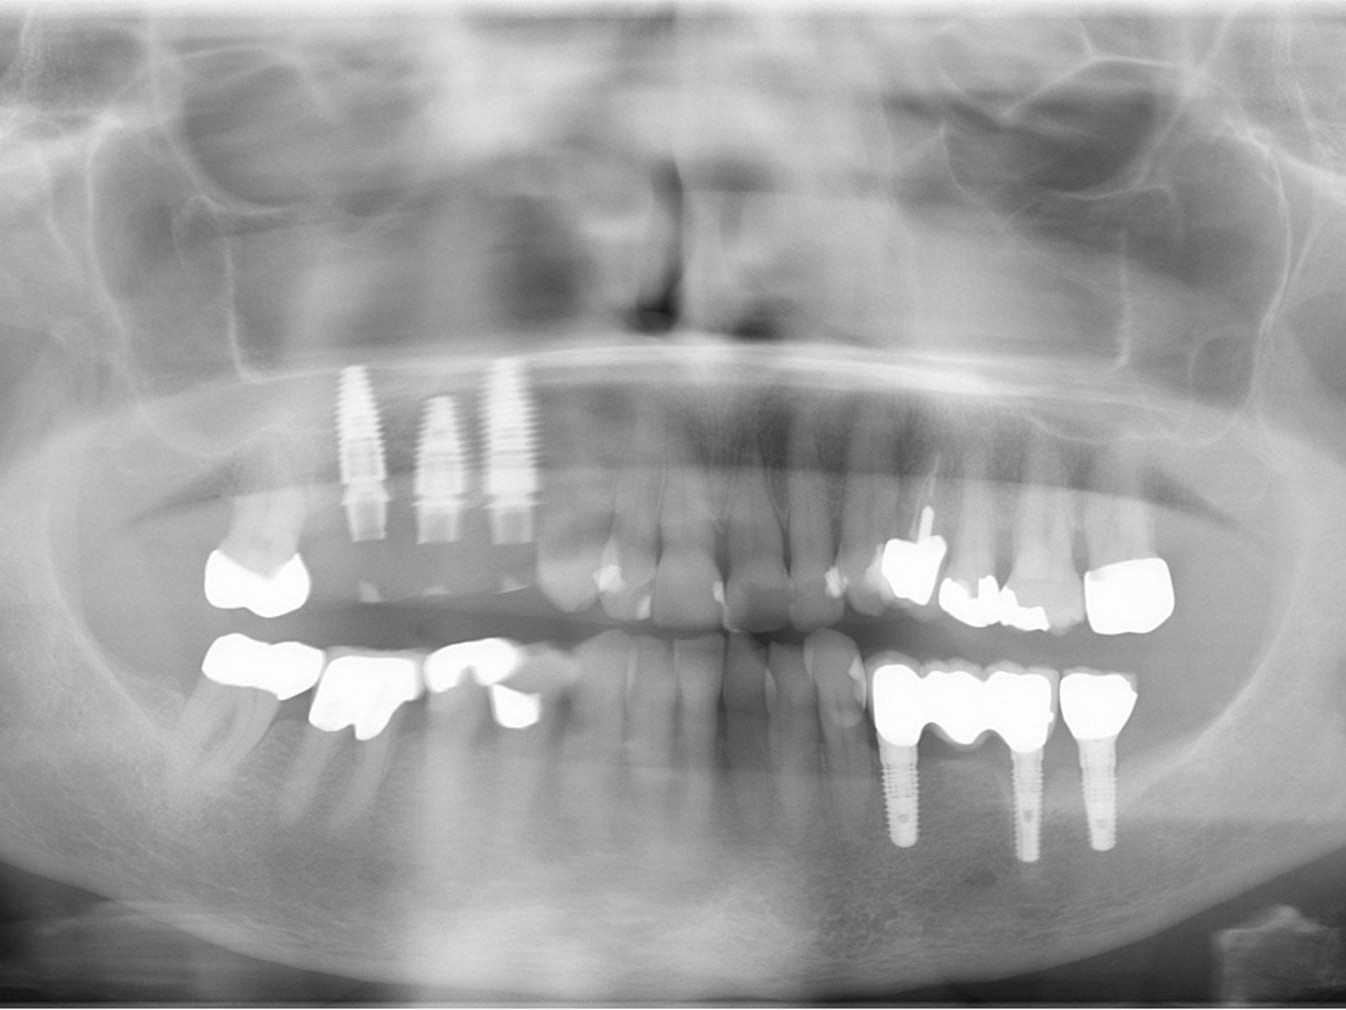

Abb. 1: Ausgangsituation Zahnfilm

Die 76-jährige Patientin stellt sich mit einer seit Jahren bestehenden Brückenversorgung im ersten Quadranten in der Praxis vor (Abb. 1). Die Pfeilerzähne 14 und 16 waren seit Jahren wurzelkanalbehandelt. Der mesiale Brückenpfeilerzahn zeigte eine apikale Beherdung mit Parodontalspaltverbreiterung. Insgesamt wies die Brücke einen Lockerungsgrad von 1 bis 2 auf. Die hauszahnärztlich angebotene erneute zahngetragene Brückenversorgung mit Ausdehnung auf den Eckzahn 13 wurde von der Patientin nicht favorisiert. Deshalb wurde der Patientin eine Entfernung der gesamten Brücke mit Sofortimplantation und Sofortversorgung in Nonokklusion angeraten (Abb. 2). Es wurden in Lokalanästhesie drei Straumann Bone Level Tapered Implantate gesetzt. In derselben Sitzung erfolgte die konventionelle Abformung beider Kiefer. Binnen 24 Stunden wurde ein verschraubtes und verblocktes Langzeitprovisorium aus PMMA auf Klebebasen (Straumann) in Nonokklusion erstellt (Abb. 3). Dieses Langzeitprovisorium verblieb 26 Monate in situ. Nach dem Entfernen des Langzeitprovisoriums zeigten sich perfekt ausgeformte Schleimhautemergenzprofile. Es wurden die entsprechenden Scanbodys eingeschraubt. Die Scandaten wurde mit dem 3Shape Trios 3 von Straumann erhoben und dem Labor übersandt (Abb. 4). Die Farbbestimmung erfolgte über den Scanner.

Abb. 20: Abschluß-OPG